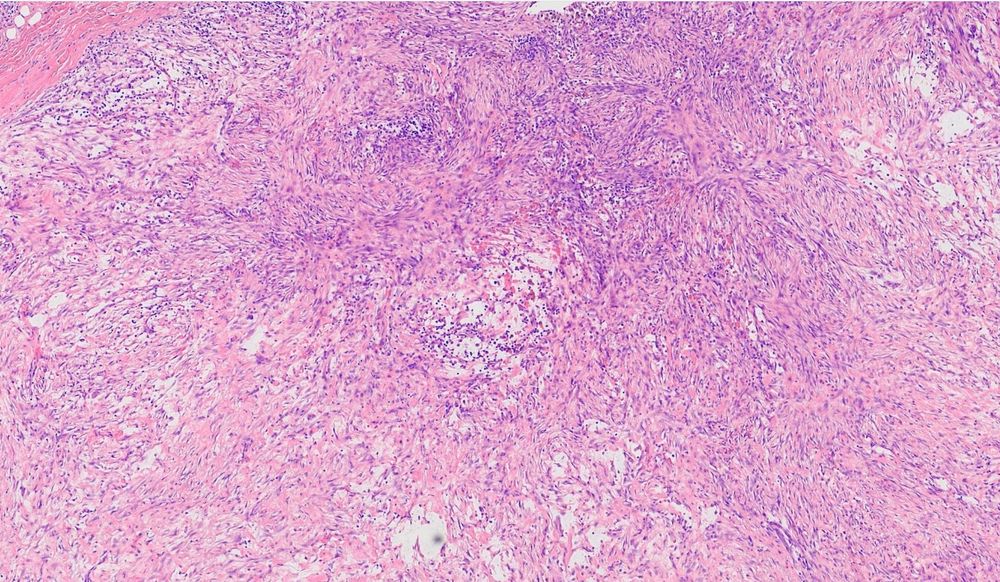

This was the biggest multinucleated giant cell of the week. SCC metastatic to bone. #SkyPath #PathSky #BSTPath #surgicalpathology